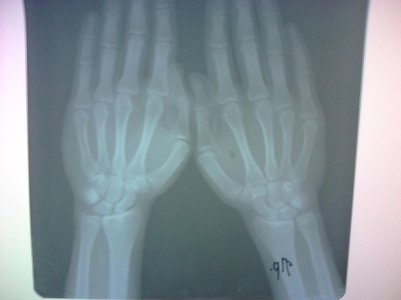

Здравствуйте. Скажите, пожалуйста, закрыты ли зоны роста на следующих снимках? Врач-эндокринолог сказала, что закрыты, но судя по прочитанным мною форумам врач может ошибаться. Врач-рентгенолог про зоны роста ничего не написала, только написала "костный возраст: 18-19 лет." Мне 18 лет, мой рост 161 см. Рост родителей: 152 см и 171 см. По направлению врача сдавал анализы на гормоны - всё в норме.